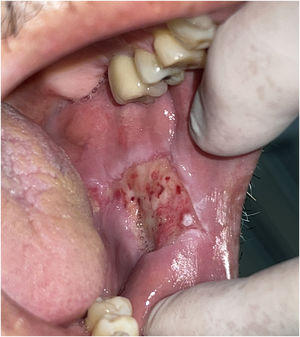

A 57-year-old male patient, a smoker (15 cigarettes a day for 43 years), showed, four years before, a painless white plaque with a slightly verrucous surface, approximately 3 cm in size, located on the left buccal mucosa (Fig. 1). Given the appearance of the lesion, the diagnostic hypothesis was leukoplakia. An incisional biopsy was performed, and smoking cessation instructions were given. Microscopic examination revealed high-grade epithelial dysplasia, corroborating the clinical diagnosis of leukoplakia (Fig. 2). Considering the lesion location and extent, the treatment of choice was complete excision using High-Power Diode Laser (TW Surgical Laser, MMOptics, São Carlos-SP, Brazil), delivering the beam with a 400 µm optical fiber, 808 nm wavelength (infrared) in continuous mode and 1.5 W power. The procedure was performed under local infiltrative anesthesia with 2% mepivacaine with vasoconstrictor (1.8 mL). For postoperative care, oral analgesics (1 g dipyrone every 12 hours in case of pain) and 0.12% chlorhexidine digluconate mouthwash, three times a day, for 14 days were prescribed. After seven days, the area appeared raw and painless (Fig. 3). After 30 days, no recurrence was observed, and complete healing of the area was noted. After 18 and 30 months (Fig. 4), clinical examination revealed no recurrence of the lesion. Despite instructions regarding smoking cessation, the patient still reports smoking, although less frequently. Therefore, continuous follow-up is essential.